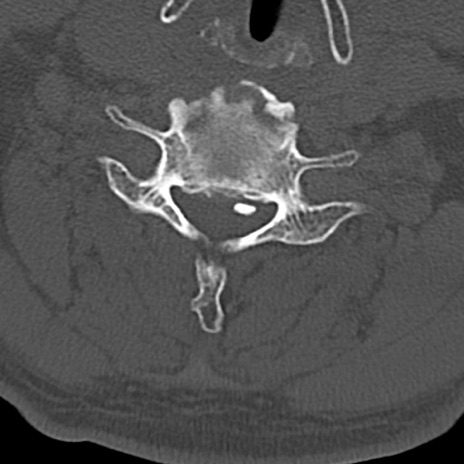

頚椎CT

横断像